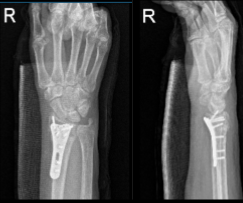

After two weeks, the patient checked in with a presented Xray and saw that osseous and metallic elements are in good alignment. Patient is still in splint but not taking any pain medications. In 4th week’s post operation, observed plate fixing the distal radius is again noted with screws holding the plate in good position.

AP and Lateral View of Patient RT 2 weeks Post-operative

AP and Lateral View of patient RT wrist 2 weeks Post-operative